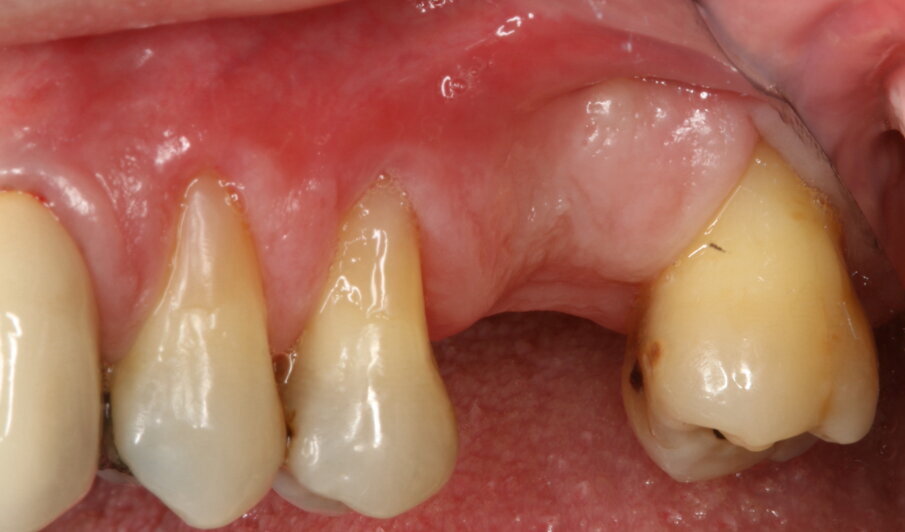

Un paziente con altezza ossea residua di 6 mm nella regione mascellare posteriore è stato sottoposto a un intervento di rialzo di seno per via transcrestale (Figg. 1, 2).

Fig. 8_Guarigione dopo 4 mesi.